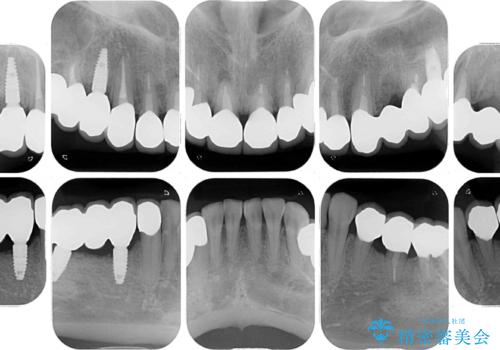

- 以前治療した歯が欠けたり、痛みを感じたりしているとのことで来院された患者様です。

アメリカ国内を転々としながら治療を行ったため治療跡がモザイク様で、クラウンが壊れていたり、抜歯が必要であったりしていました。

上下左右すべての奥歯に処置が必要であり、同時に行うと食事が取りにくくなってしまったり、手前の歯に負担がかかって初診時よりも状況が悪化したりする可能性があるため、片方ずつ処置を進めて行くこととしました。

下顎右側は骨造成を併用してインプラント治療を行い、その他の奥歯もインプラントや歯周外科処置を併用して補綴治療を進め、最後に前歯部の欠けてしまったセラミッククラウンを作り替えることとしました。